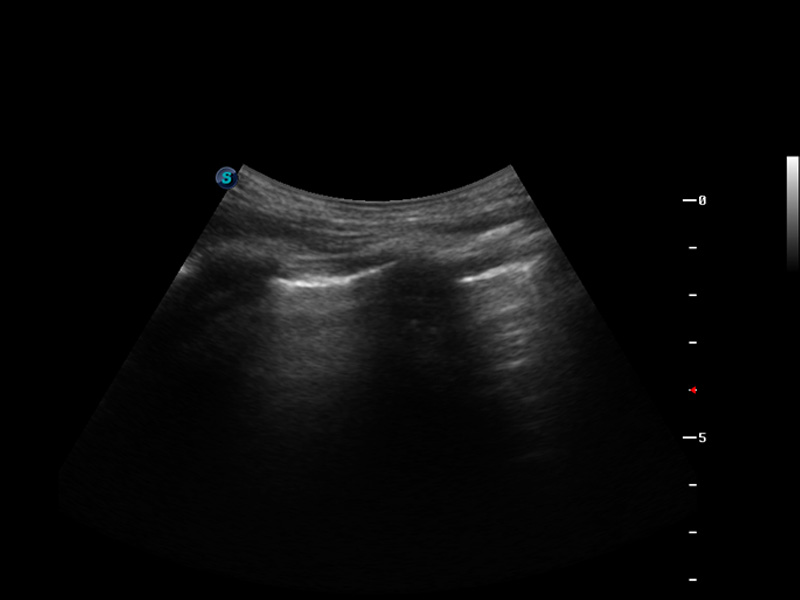

S9便携式彩色多普勒超声诊断仪是云顶集团官网研发的高端便携彩超设备,外观设计新颖、产品性能卓越。S9在便携超声领域采用了突破传统的触摸屏交互设计,并以先进的软件硬件技术和设计理念,为您带来清晰的图像质量、稳定的工作性能和便捷的操作体验。

μ-Scan微米成像